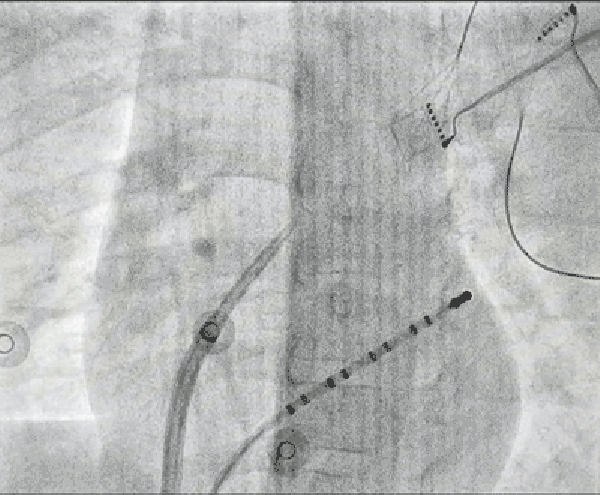

通常情况下,成人选用逆行主动脉法(经股动脉、主动脉瓣)将消融导管送达“短路”区域,但损伤患儿大动脉和主动脉瓣风险高,团队另辟蹊径:穿刺房间隔,经左心房顺行途径消融“短路”区,需要小心谨慎穿刺房间隔,在左心房内稳定操作消融导管,精细定位“短路”区,消融成功,安全、精准地“拆解”了心内异常电路。

房间隔穿刺影像,红色箭头为房间隔穿刺点